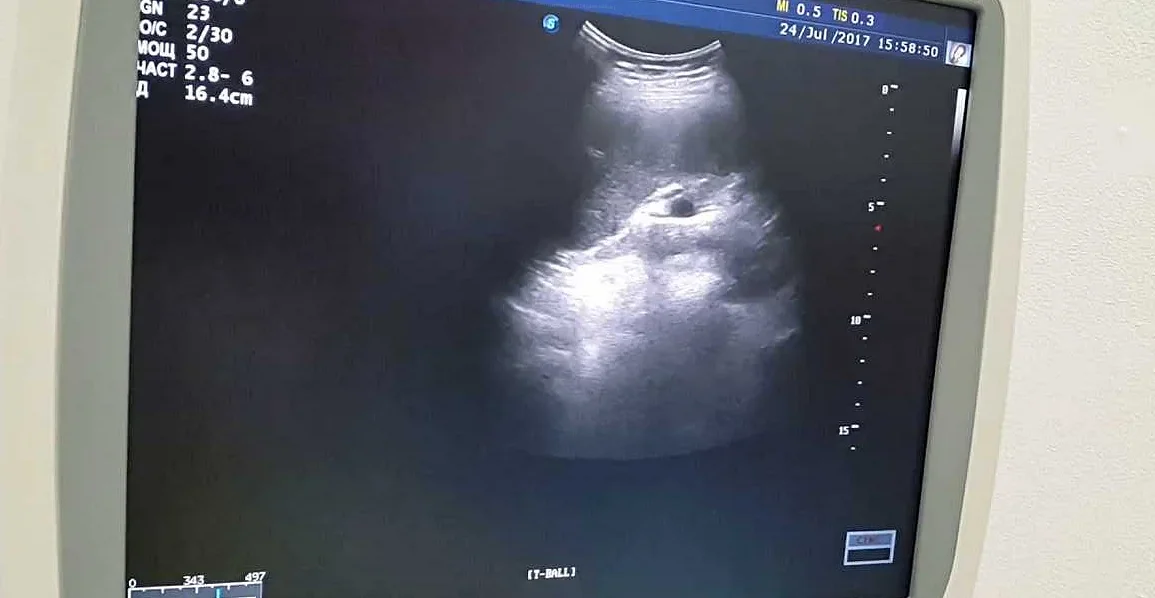

Одним из основных методов диагностики является ультразвуковое исследование (УЗИ) селезенки. УЗИ позволяет получить детальную информацию об изменениях в селезенке, в том числе об образовании кальцинатов. Этот метод неинвазивен, безопасен и позволяет определить размеры и структуру селезенки.

• УЗИ органов брюшной полости — позволяет визуализировать размеры, структуру и возможные изменения в селезенке. Кальцинаты могут быть обнаружены на УЗИ.

Кальцинаты селезенки обычно являются случайной находкой при проведении рентгенологических исследований, таких как УЗИ или рентген селезенки. В большинстве случаев они не вызывают никаких симптомов и не требуют особого лечения. Однако, в некоторых случаях, кальцинаты могут быть связаны с определенными заболеваниями или могут вызывать дискомфорт или боли в области селезенки.